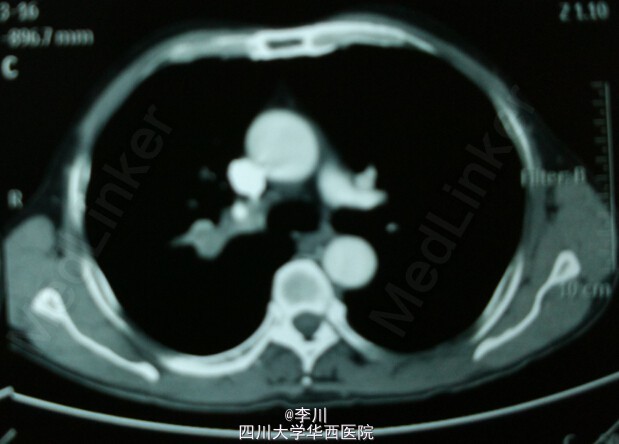

在全麻下行VATS右肺上叶切除术+支气管袖式成形术+淋巴结清扫术,术中见肿块位于右肺上叶支气管开口,约1.5cm*1.5cm*1.2cm大小,无脏层胸膜皱缩、无侵犯壁层胸膜;肿瘤距隆突 <2cm,2、3、4、7、9、11、12、13组淋巴结肿大。术后患者送人胸外ICU,予以呼吸机辅助呼吸、心电监护、抗感染、祛痰等对症支持治疗。

肺癌患者癌变位于一个肺叶内,但已侵及局部主支气管或中间支气管,为了保留正常的邻近肺叶,避免作一侧全肺切除术,可以切除病变的肺叶及一段受累的支气管,再吻合支气管上下切端,临床上称为支气管袖状肺叶切除术。对于胸外科医生来说,该手术难度大,对主刀医生要求很高。以往此类手术常常开胸手术,随着近年来胸腔镜的发展,胸腔镜支气管袖式成形、肺动脉袖式成形术也非常成熟。